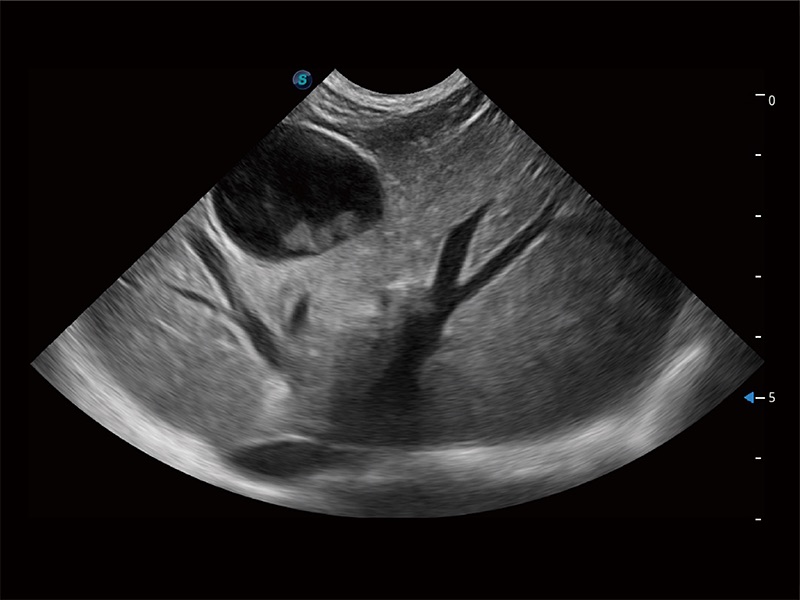

高性能和先进的临床应用工具可以为动物医生提供临床信心。ProPet 80 搭载了先进的腹部和浅表应用工具,帮助医生在日常临床实践中发挥前所未有的作用。

极大提升超低速微细血流的检出能力,同时更精准地滤除软组织和超声信号,为兽用医生提供以往无法通过常规血流获得的疾病诊断信息。

在传统二维血流成像的基础上,呈现血流的立体感,具有动感的生命力之美。即便是微小的血管也能轻松应对,提高了血流的视觉敏感性。

ProPet 80 全新的动物超声智能软件和丰富的探头群,为动物医生提供了高清晰度和精细分辨率的图像,无论在宠物、马科、畜牧还是实验室动物等应用中都可以轻松应对,为您的日常工作带来满意的体验。